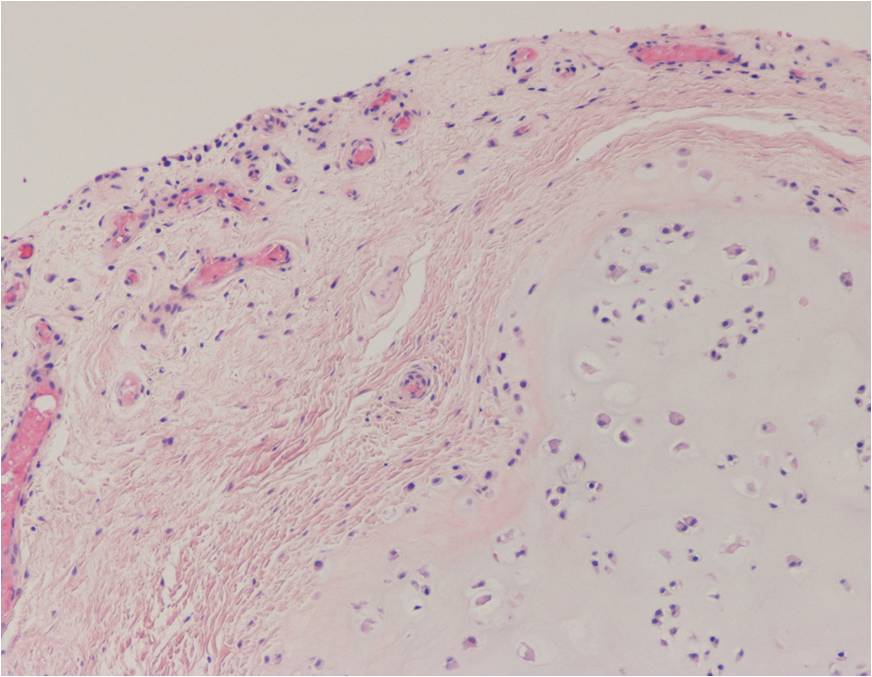

Synovial chondromatosis is an uncommon, benign, process that occurs in large joints, such as the knee (50%), hip, elbow, or shoulder. This process mainly affects synovium and hence most commonly arises from joints and tendons which are lined by synovium. Synovial Chondromatosis may also affect bursae and extend into surrounding soft tissues. This condition is seen in patients between 20 and 50 years of age and most commonly in men (male-female ratio of 2-4/1). The patient usually complains of pain, stiffness, crepitance, swelling, and joint locking. The knee is the most common site to be affected. Symptoms are long-standing and progressive. The plain x-ray may be normal (5 to 33%) or there may be small flecks of calcification (Fig. 1 & 2). On MRI the nodules of cartilage are easily seen. MR imaging may also show synovial thickening, joint erosions and intraarticular calcifications. The signal characteristics of these intraarticular bodies depend of their composition. If mineralization is not present the signal intensity follows the cartilage signal with intermediate signal on T1 images and high signal on T2 weighted MR images. Uniformly calcified bodies follows bone density on all sequences with bone marrow signal centrally and low signal peripherally (Fig. 3-5). Histologically the cartilage is arranged in nodules, which are quite cellular (Fig. 7-9). Synovial lining is present surrounding the cartilage nodules (Fig. 8). The cartilage nodules are often referred to as loose bodies however they are not really loose and embedded in the synovium lining. This is considered a metaplastic condition as opposed to a true neoplastic condition. Rarely it may turn into a malignancy usually a low grade chondrosarcoma. Malignant change is suggested by deep erosions into adjacent bone.

Fig. 7 – 9. Microscopic Pathology. Low (Fig. 7) and intermediate (Fig. 8 & 9) magnification demonstrates nodules of cartilage with high cellularity. Synovial lining is present surrounding the cartilage nodules.